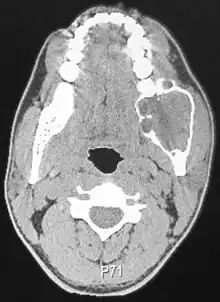

A CT scan of a patient with an ameloblastoma.